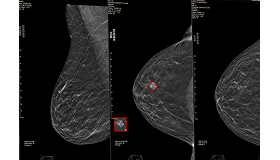

SecondLook® Detection for 2D Mammography

Developed for 2D mammography, SecondLook’s Detection solution automatically marks suspicious lesions, identifying potential cancers and microcalcifications. The solution provides the radiologist with a “second look” which helps detect actionable missed cancers earlier than screening mammography alone, providing workflow enhancements and improved efficiency.